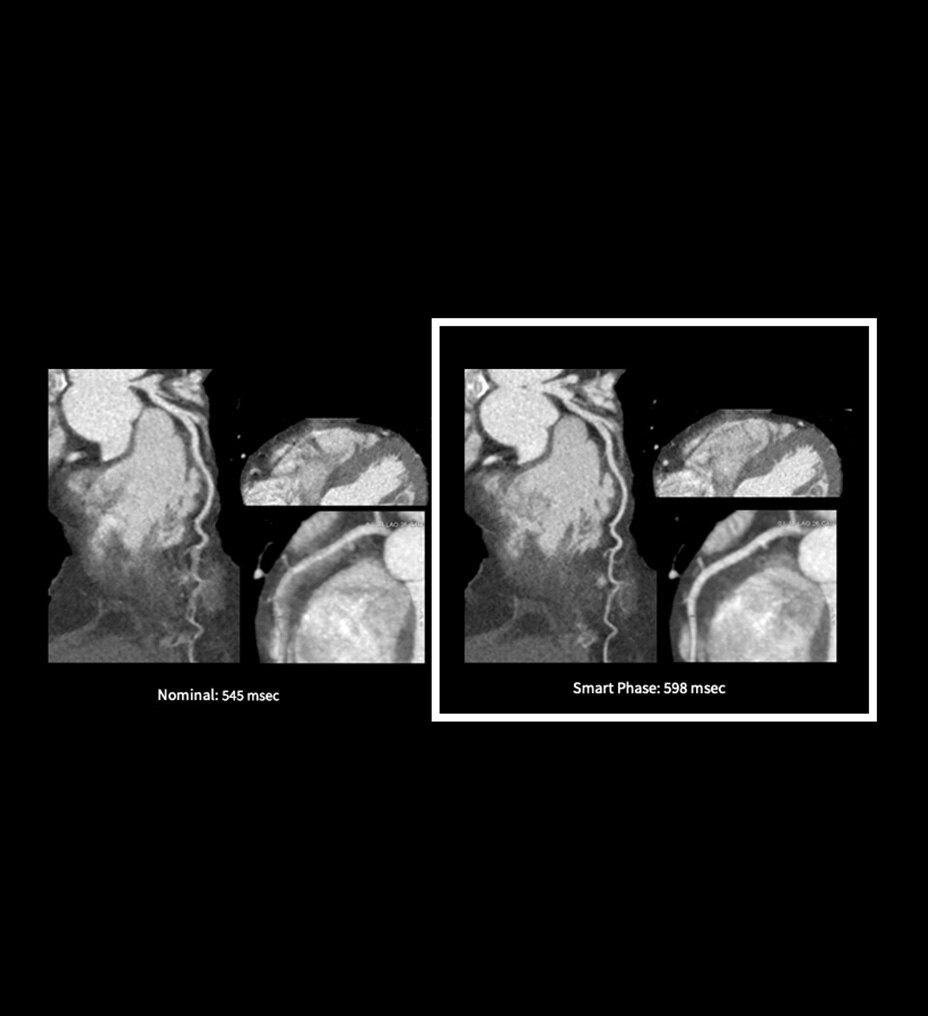

Smart Phase is a reconstruction feature designed to intelligently select the best cardiac phase for image reconstruction. This ensures improved image quality with the least motion and enhances workflow by reducing the need for manual phase adjustments.